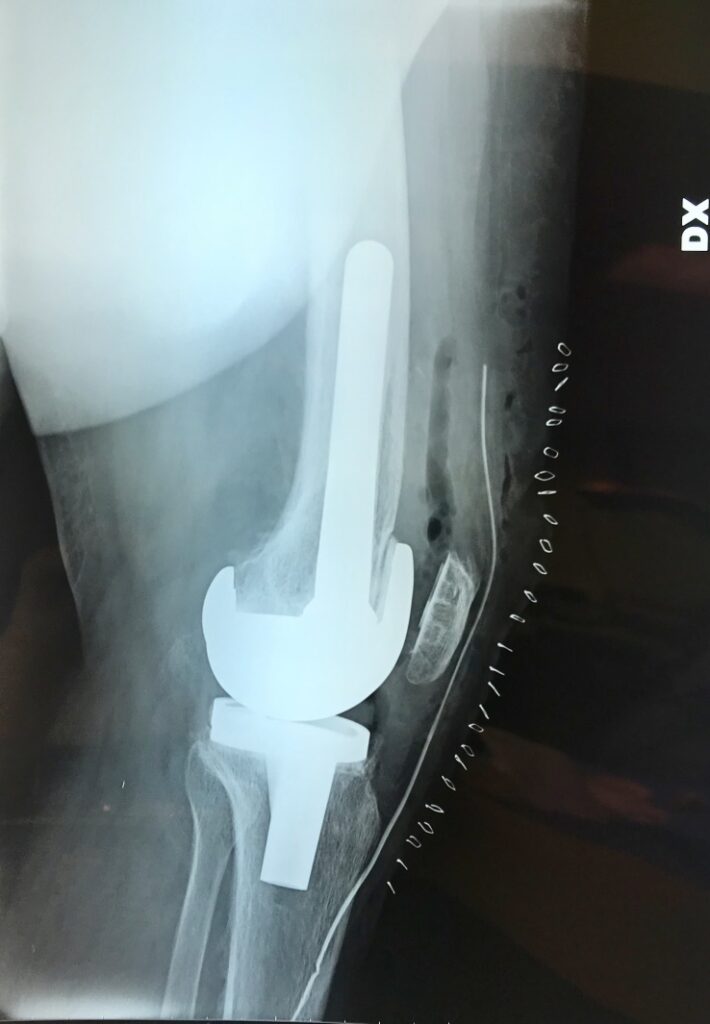

- Il ginocchio di Giuseppe, ormai nostro Amico : operato al Nord , si infetta . Tutti lo rifiutano. Nessuno lo vuole accogliere. Il Nostro Reparto , il Nostro Ospedale , SI! Una storia……per fortuna a lieto fine.

radiografie con la protesi di ginocchio reimpiantata : oggi Giuseppe guida la Sua auto sportiva.